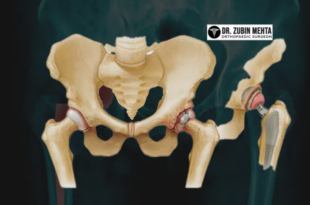

Hip pain severely hinders daily activities and overall quality of life. However, the relentless march of medical technology has introduced robotic total hip replacements as one of the best treatment options on the market. For patients looking for robotic total hip replacement in Mohali, COJRI combines years of expertise and …

Read More »Multi-Speciality Hip Replacement Hospital in Chandigarh with Latest Techniques

When hip pain interferes with normal activities, it is important to find a hospital where one can get long-term relief from pain and restore mobility. For multi-specialty hip replacement hospitals in Chandigarh, Dr. Zubin Ortho is reputed for providing advanced orthopedic services and patient-centric care. Why Opt for a Multispecialty …

Read More »Top Hip Replacement Loosening Treatment Chandigarh with Expert Orthopedic Care

Patients regain mobility and live without pain after undergoing a hip replacement. Although, in some cases, hip replacement patients may have a complication where the implant becomes loose. If after receiving a hip replacement and are experiencing discomfort, it is necessary to seek further care. Cojri provides advanced, reliable, and …

Read More »Hip Replacement Hospital in Chandigarh with Experienced Surgeons & Modern Technology

When you have pain that affects your daily life you need to get the right medical care. Finding the Hip Replacement Hospital in Chandigarh can make a big difference in how well you recover, how mobile you are and your overall quality of life. Hip replacement surgery is a good …